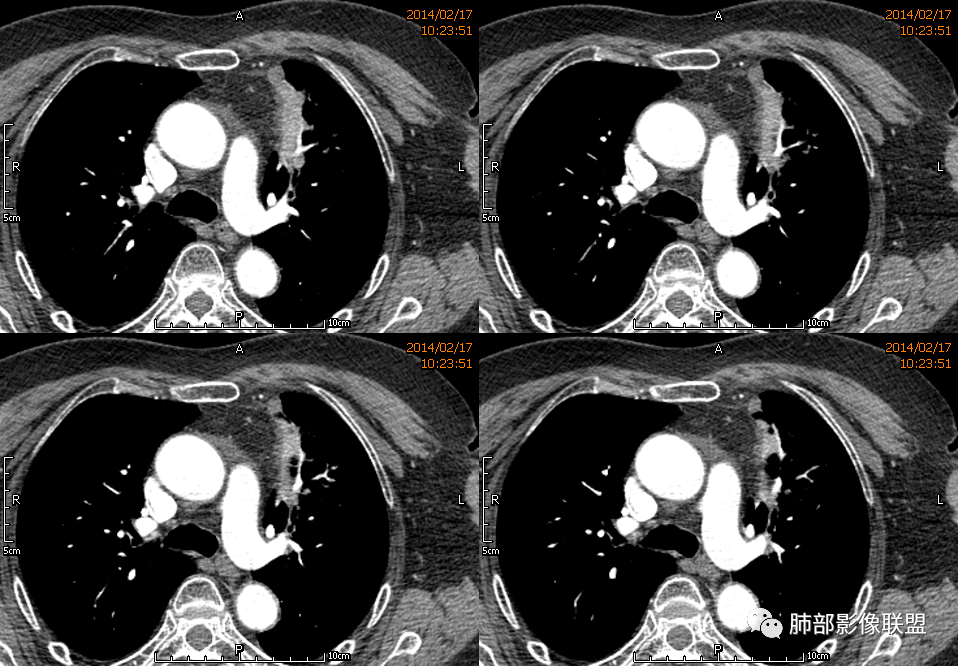

薏米: 老年女性,急性起病,咳嗽,咳痰,咯血,白细胞低,胸部CT提示左肺上叶可见一团块样密度增高影,边缘平直,部分略有膨隆,内可见支气管进入后截断,小的空洞,血管造影,坏死,明显强化,周边可见少许索条,考虑炎性病变,肺脓肿可能。鉴别结核,隐球菌。

一切∮随缘: 定位:肺内,左肺上叶肿块,呈长条状,平行血管束生长,边缘分叶,平扫密度均匀,增强后不均匀强化,可见低密度坏死,近段支气管及血管穿行病灶内,远端堵塞支气管,血管似有破坏,周围散在点状小结节,及纤维索条影,考虑恶性:腺癌,类癌,淋巴瘤。鉴别结核及隐球菌。

红星: 老年女性,咳嗽咳痰10天,痰中带血4天。左肺上叶前段胸膜下肿块影,沿支气管方向走行以膨胀生长为主,局部有收缩改变,支气管血管绝断,中间有小片状的坏死及小的空洞影,增强扫描病灶明显的强化,病灶周围网格状的小叶间隔增厚。拟左肺上叶前段浸润型腺癌并癌性淋巴管炎。鉴别诊断结核肉芽肿。

秦化君: 左肺上叶前段胸膜下软组织密度肿块影,边缘清晰,部分边缘膨隆,纵隔缘弧形内凹,脂肪界面清晰。肿块中心密度减低,支气管进入病灶后截断,似有扩张表现,病灶周围可见小叶间隔增厚,斑片影,近端支气管似管壁增厚。增强后明显强化,中心见低密度区。考虑:1.肉芽肿性炎?2.IMT?3.淋巴瘤?

傅昌瑜: 老年女性,咳嗽咳痰10天,痰中带血4天。左肺上叶前段胸膜下肿块影,沿支气管方向走行,膨胀生长为主,局部边缘似有收缩改变,中间有小片状的坏死,支气管进入,增强扫描病灶明显的强化,血管走形较自然(血管漂浮征?),病灶周围网格状的小叶间隔增厚。考虑淋巴瘤可能性大,注意鉴别炎性肉芽肿及肺腺癌。

水晶石头: 患者老年女性,咳嗽咳痰10天,痰中带血4天余。查血常规白细胞低;肿瘤标志物、凝血功能正常;血生化:蛋白低;C反应蛋白、血沉稍升高。胸部CT:左肺上叶前段胸膜下沿气管支气管走形肿块影,长轴与胸膜平行,见分叶、毛刺、支气管截断、空泡征象。增强明显强化,且见血管造影征及病灶内小灶低密度坏死区。左肺上叶尖后段见一结节灶。综合考虑恶性病变可能大,腺癌或淋巴瘤可能。鉴别诊断肺脓肿。

尘缘: 老年女性,咳嗽咳痰10天,痰中带血4天,白细胞及中性粒明显减低,轻度贫血。影像表现:左上叶肿块,边缘膨隆,局部平直,支气管稍扩张,进入后远端堵塞,内见小空洞及不规则坏死区,增强后强化明显,坏死边界较清,并见环状强化区,内部血管走行自然,周围见小叶间隔增厚呈大网格征。初步诊断:慢性炎性伴脓肿形成及肉芽组织增生。鉴别淋巴瘤及腺癌,先抗炎治疗后复查或直接穿刺明确。

张延军: 左肺上叶前段软组织影,偏下缘见充气支气管,部分支气管壁与肿块近端增厚狭窄。实性部分见血管穿行,边缘平直并局限性凹陷,增强扫描内见斑片状低密度区,界不清,实性部分中度强化,病变外宽内窄,基底贴于胸壁,周围肺组织内见条片状密度增高影,考虑炎性,结核?腺癌待排。

毛勤香: 老年女性,左肺上叶胸膜下肿块,部分膨隆部分收缩,边缘毛糙模糊,周围少许索片状影,小叶间隔增粗,支气管进入后截断,增强扫描明显不均匀强化,内低密度区无明显强化,血管走行尚可,首先考虑感染性变并脓肿形成,鉴别淋巴瘤,建议抗炎后复查。

王崇军: 老年女性,咳嗽咳痰10天,痰中带血4天。左肺上叶前段胸膜下 肿块影及段形态密度增高影,沿支气管方向走行,膨胀生长为主,局部有收缩改变,支气管进入并闭塞,中间有小片状的坏死及小的空洞影,空洞漂浮在坏死边缘,增强扫描病灶明显的强化,坏死边界清楚,似乎有轻度强化环,病灶周围网格状的小叶间隔增厚及小结节影,外侧胸膜呈糊墙改变。考虑为肺脓肿,这么大的病灶,竟然没有发烧,白细胞低,CPR轻度升高,均与脓肿不符,所以恶性待排,短期抗炎治疗后复查,病灶没有变化,脓肿就可以排除,恶性基本可以确定。

王武章: 灶内低密度,花环样强化,血管穿行漂浮,邻近胸膜并未广泛增厚也未牵拉但接触面脂肪密度略高且模糊。考虑IMT,鉴别慢性炎症相关的非特异性瘤样病变。

1、坏死区环形强化,指向慢性脓肿。

2、坏死区有血管,基本排除结核。

3、这个卫星灶,更进一步定了大方向,炎性。

※综上所述,看到这四幅图,基本能够准确诊断炎性※